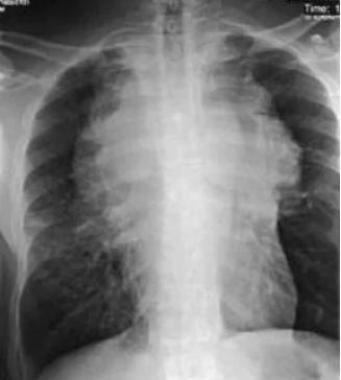

5、巨大肿块形:单侧或对侧,致密,外带密度逐渐减低,占据整个上肺野及部分中肺野,下缘清晰锐利,外缘模糊。如下图8所示。

图8示:巨大肿块样的胸腺影

(2)正常胸腺影有时需要与胸腺囊肿、淋巴瘤、胸腺瘤、畸胎瘤及胸腺脂肪瘤等加以鉴别。如下图9、10所示。

图9示:一个分叶状胸腺淋巴瘤.(图片来自Medscape)

图10示:位于右心缘的胸腺瘤. (图片来自Medscape)